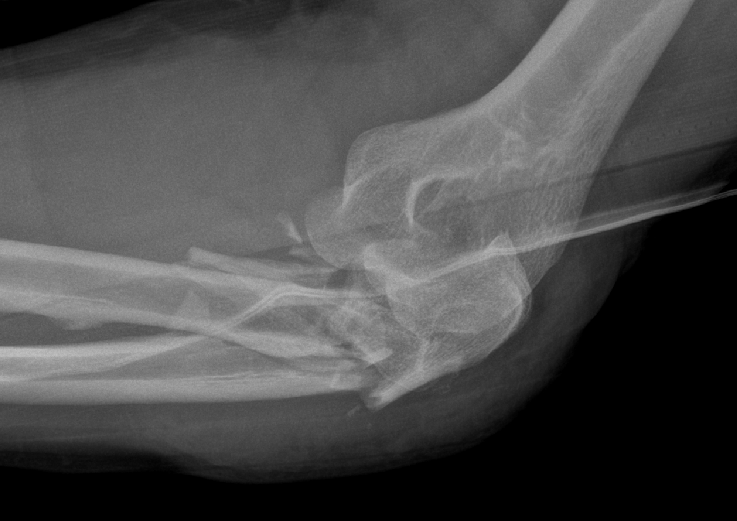

Orthopedic Surgeon with special interest in joint preservation